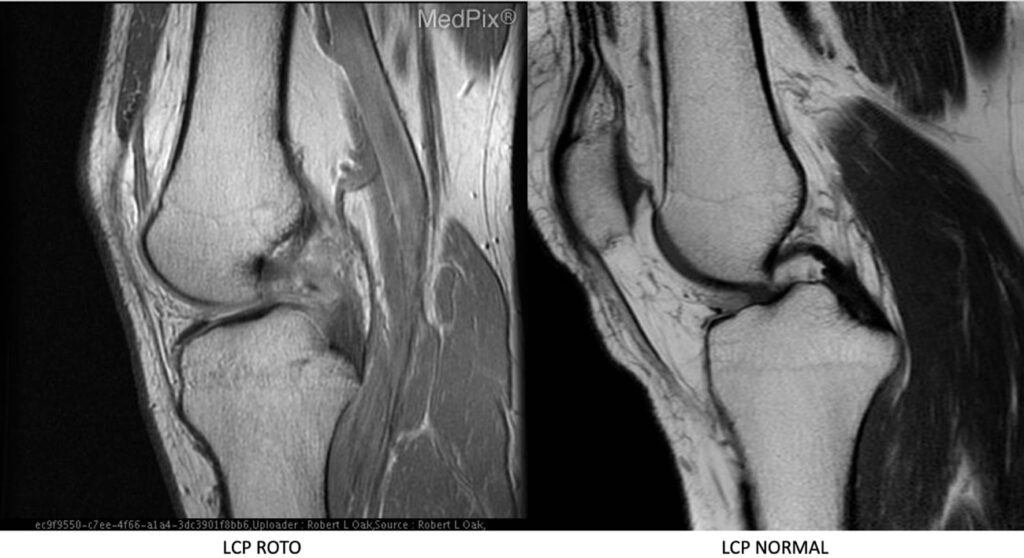

Entres os exames destacam-se a radiografia sob estresse e a ressonância magnética.